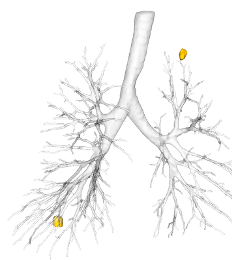

Patient eligibility and post-procedural assessment for Bronchial Lung Volume Reduction therapies

BLVR using one-way endobronchial valves is a highly effective treatment for patients with severe emphysema. However, procedural success also depends on an accurate selection of patients without collateral ventilation and sensitive post-treatment monitoring.

By leveraging Thirona’s AI-enabled quantitative assessment of interlobar fissure integrity, the presence or absence of collateral ventilation can be confirmed. Its accuracy correlates with the assessment made by Chartis System. The non-invasive tool can serve as a important biomarker to determine the patient eligibility of the therapy and significantly optimizing the selection process. Following the procedure, Thiona’s new analysis provides an automated detection and localization of endobronchial implants, enabling a more efficient evaluation of valve placement and longitudinal follow-up.